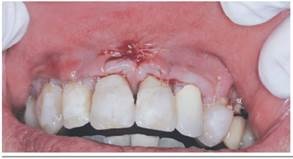

En la figura 4 se observa que ambos injertos logran mejorar el biotipo gingival, sin embargo, con el ITC se obtuvo mayor volumen gingival (fig.5).

El resultado estético, evaluado en la Tabla 2 mediante el Root Esthetic Score (RES), muestra resultados similares. En relación al color y contorno del margen gingival (CMG), textura de los tejidos blandos (TTB), alineación de la unión mucogingival (UMG) y color de la encía (CE), Mucograft® obtuvo mejores resultados. Se observan diferencias en la posición del margen gingival (PMG), donde en la 1.2 (Mucograft®) se observó menor recubrimiento que la 2.2 (ITC), y en la 1.3 (Mucograft®) mayor que la 2.3 (ITC).